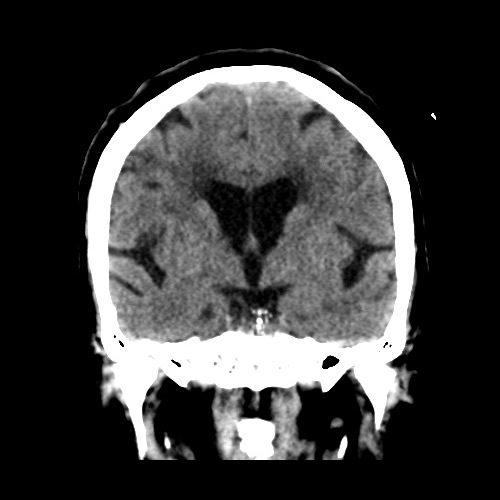

Femenino, 71 años. Sospecha de ACV agudo.